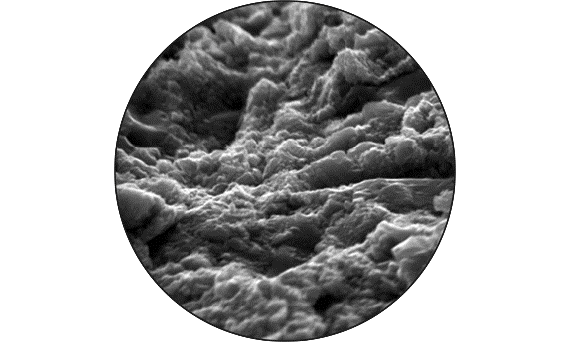

Lassen Sie sich von unserer Erfolgsbilanz inspirieren: Wir haben den Standard in puncto Knochenerhalt gesetzt. Aufbauend auf dem bewährten Renommee des Astra Tech Imlant Systems für eine schnelle, vorhersagbare Osseointegration. Die OsseoSpeed-Oberfläche beitet langfristigen Knochenerhalt und übertrifft zwei andere Implantat-Oberflächen in Bezug auf marginalen Knochenerhalt in 1-Jahres- und 5-Jahres-Follow-ups.*

Die Hauptmerkmale des Implantats – EV-Innenverbindung, OsseoSpeed, MicroThread, Soft Tissue Chamber – wurden für das Astra Tech Implant System hinsichtlich Knochenerhalt und Ästhetik dokumentiert und klinisch erprobt.

OsseoSpeed - stärkere und schnellere Osseointegration